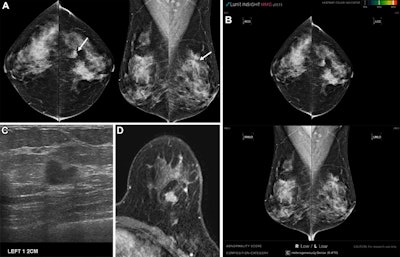

Images in a 42-year-old asymptomatic woman. (A) Digital mammograms show an irregular spiculated mass in the left upper outer quadrant (arrows). (B) Artificial intelligence (AI) software did not mark this lesion due to a low abnormality score. (C) Ultrasound and (D) breast MRI scans revealed a 1.1-cm irregular mass in the left upper outer breast at the 1-o'clock position. Breast-conserving surgery was performed; the lesion was confirmed as a 1.1-cm invasive ductal carcinoma (luminal subtype, histologic grade 3) without axillary lymph node metastasis. The lesion was classified as actionable; three radiologists categorized it as suspicious. The reason for the AI miss was that the lesion was obscured by overlying dense breast tissue. CC = craniocaudal, MLO = mediolateral. Images and caption courtesy of the RSNA.